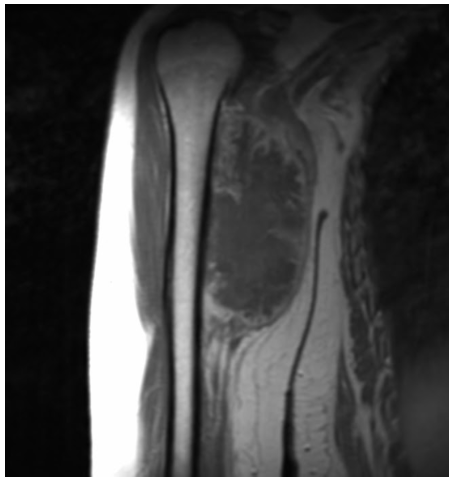

Radiographic imaging is used to help form a diagnosis. These include X-Ray, MRI, CT and Bone Scans

An example of an MRI is shown.